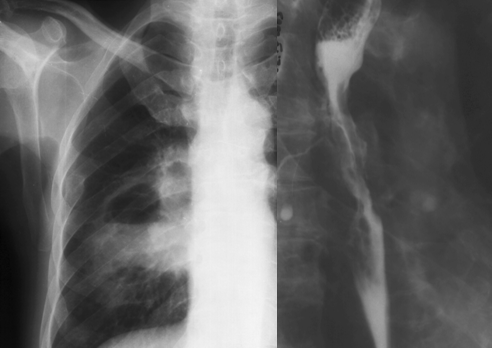

Figure 2. Plain thoracic X-Ray and esophagogram in a case with esophageal cancer associating aero-digestive fistula and pulmonary absce 222f56c ss.